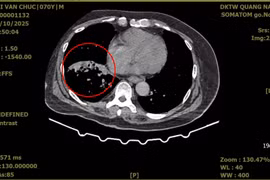

(khoahocdoisong.vn) - Ho ra máu do giãn động mạch phế quản là biến chứng nặng, tỉ lệ tái phát cao và dễ tử vong do suy hô hấp hoặc mất máu. Nút mạch là một kỹ thuật cao, ít xâm lấn lần đầu tiên được Bệnh viện Việt Nam -Thụy Điển Uông Bí triển khai thành công.